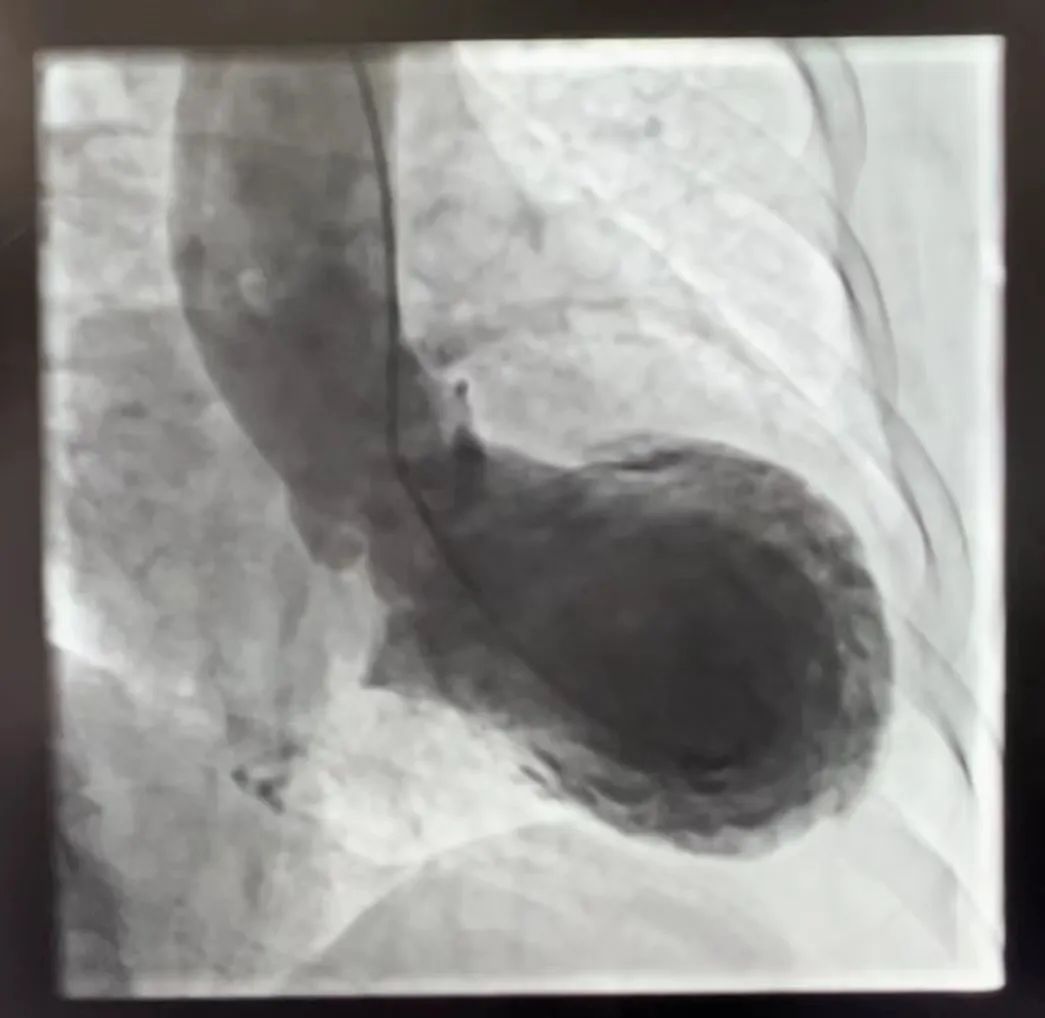

冠状动脉造影下的“章鱼罐”心脏

不过蹊跷的是,冠脉造影显示患者的心脏血管并没有明显堵塞,冠脉的血流非常通畅,这与引起急性心肌梗死的血管堵塞病情不相符。“这样严重的症状不可能没有问题。”区人民医院心血管内科副主任医师倪挺立即联动介入团队,对患者进行左心室造影术,果然发现患者的左心室前壁、基底部、心尖部收缩活动消失。“失去‘动力’心脏缩成球状,在造影下就像一只章鱼。”看到此情此景,倪挺立刻判断,“这是心尖球样综合征,章鱼心呀,心脏就像一个装着章鱼的罐子一样。”并立即优化治疗方案,及时挽救了患者生命。

心脏变成“章鱼罐”,区人民医院心血管内科主任、胸痛中心负责人王明亮告诉记者,“章鱼罐”心脏的专业名称叫心尖球样综合征,原名为“Tako-tsubo综合征”,又被称为应激性心肌病、心碎综合征,是一种以左心室短暂节段性收缩功能障碍为特征的综合征,类似于心肌梗死(MI),但没有阻塞性冠状动脉疾病或急性斑块破裂的血管造影证据。该疾病由日本学者首次报道,因为在心室造影中左心室形状类似日本渔民用来捕捉章鱼的罐子而得名。